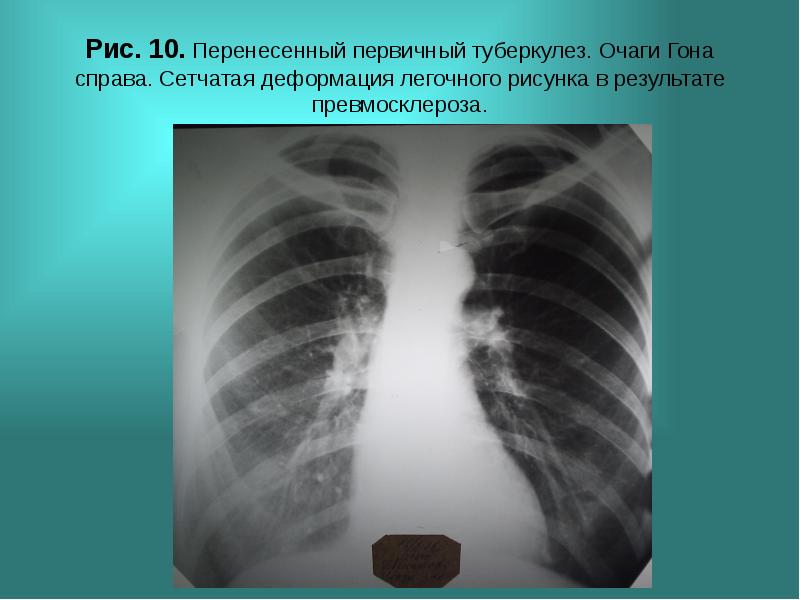

Ячеистая деформация легочного рисунка: медицинская визуализация